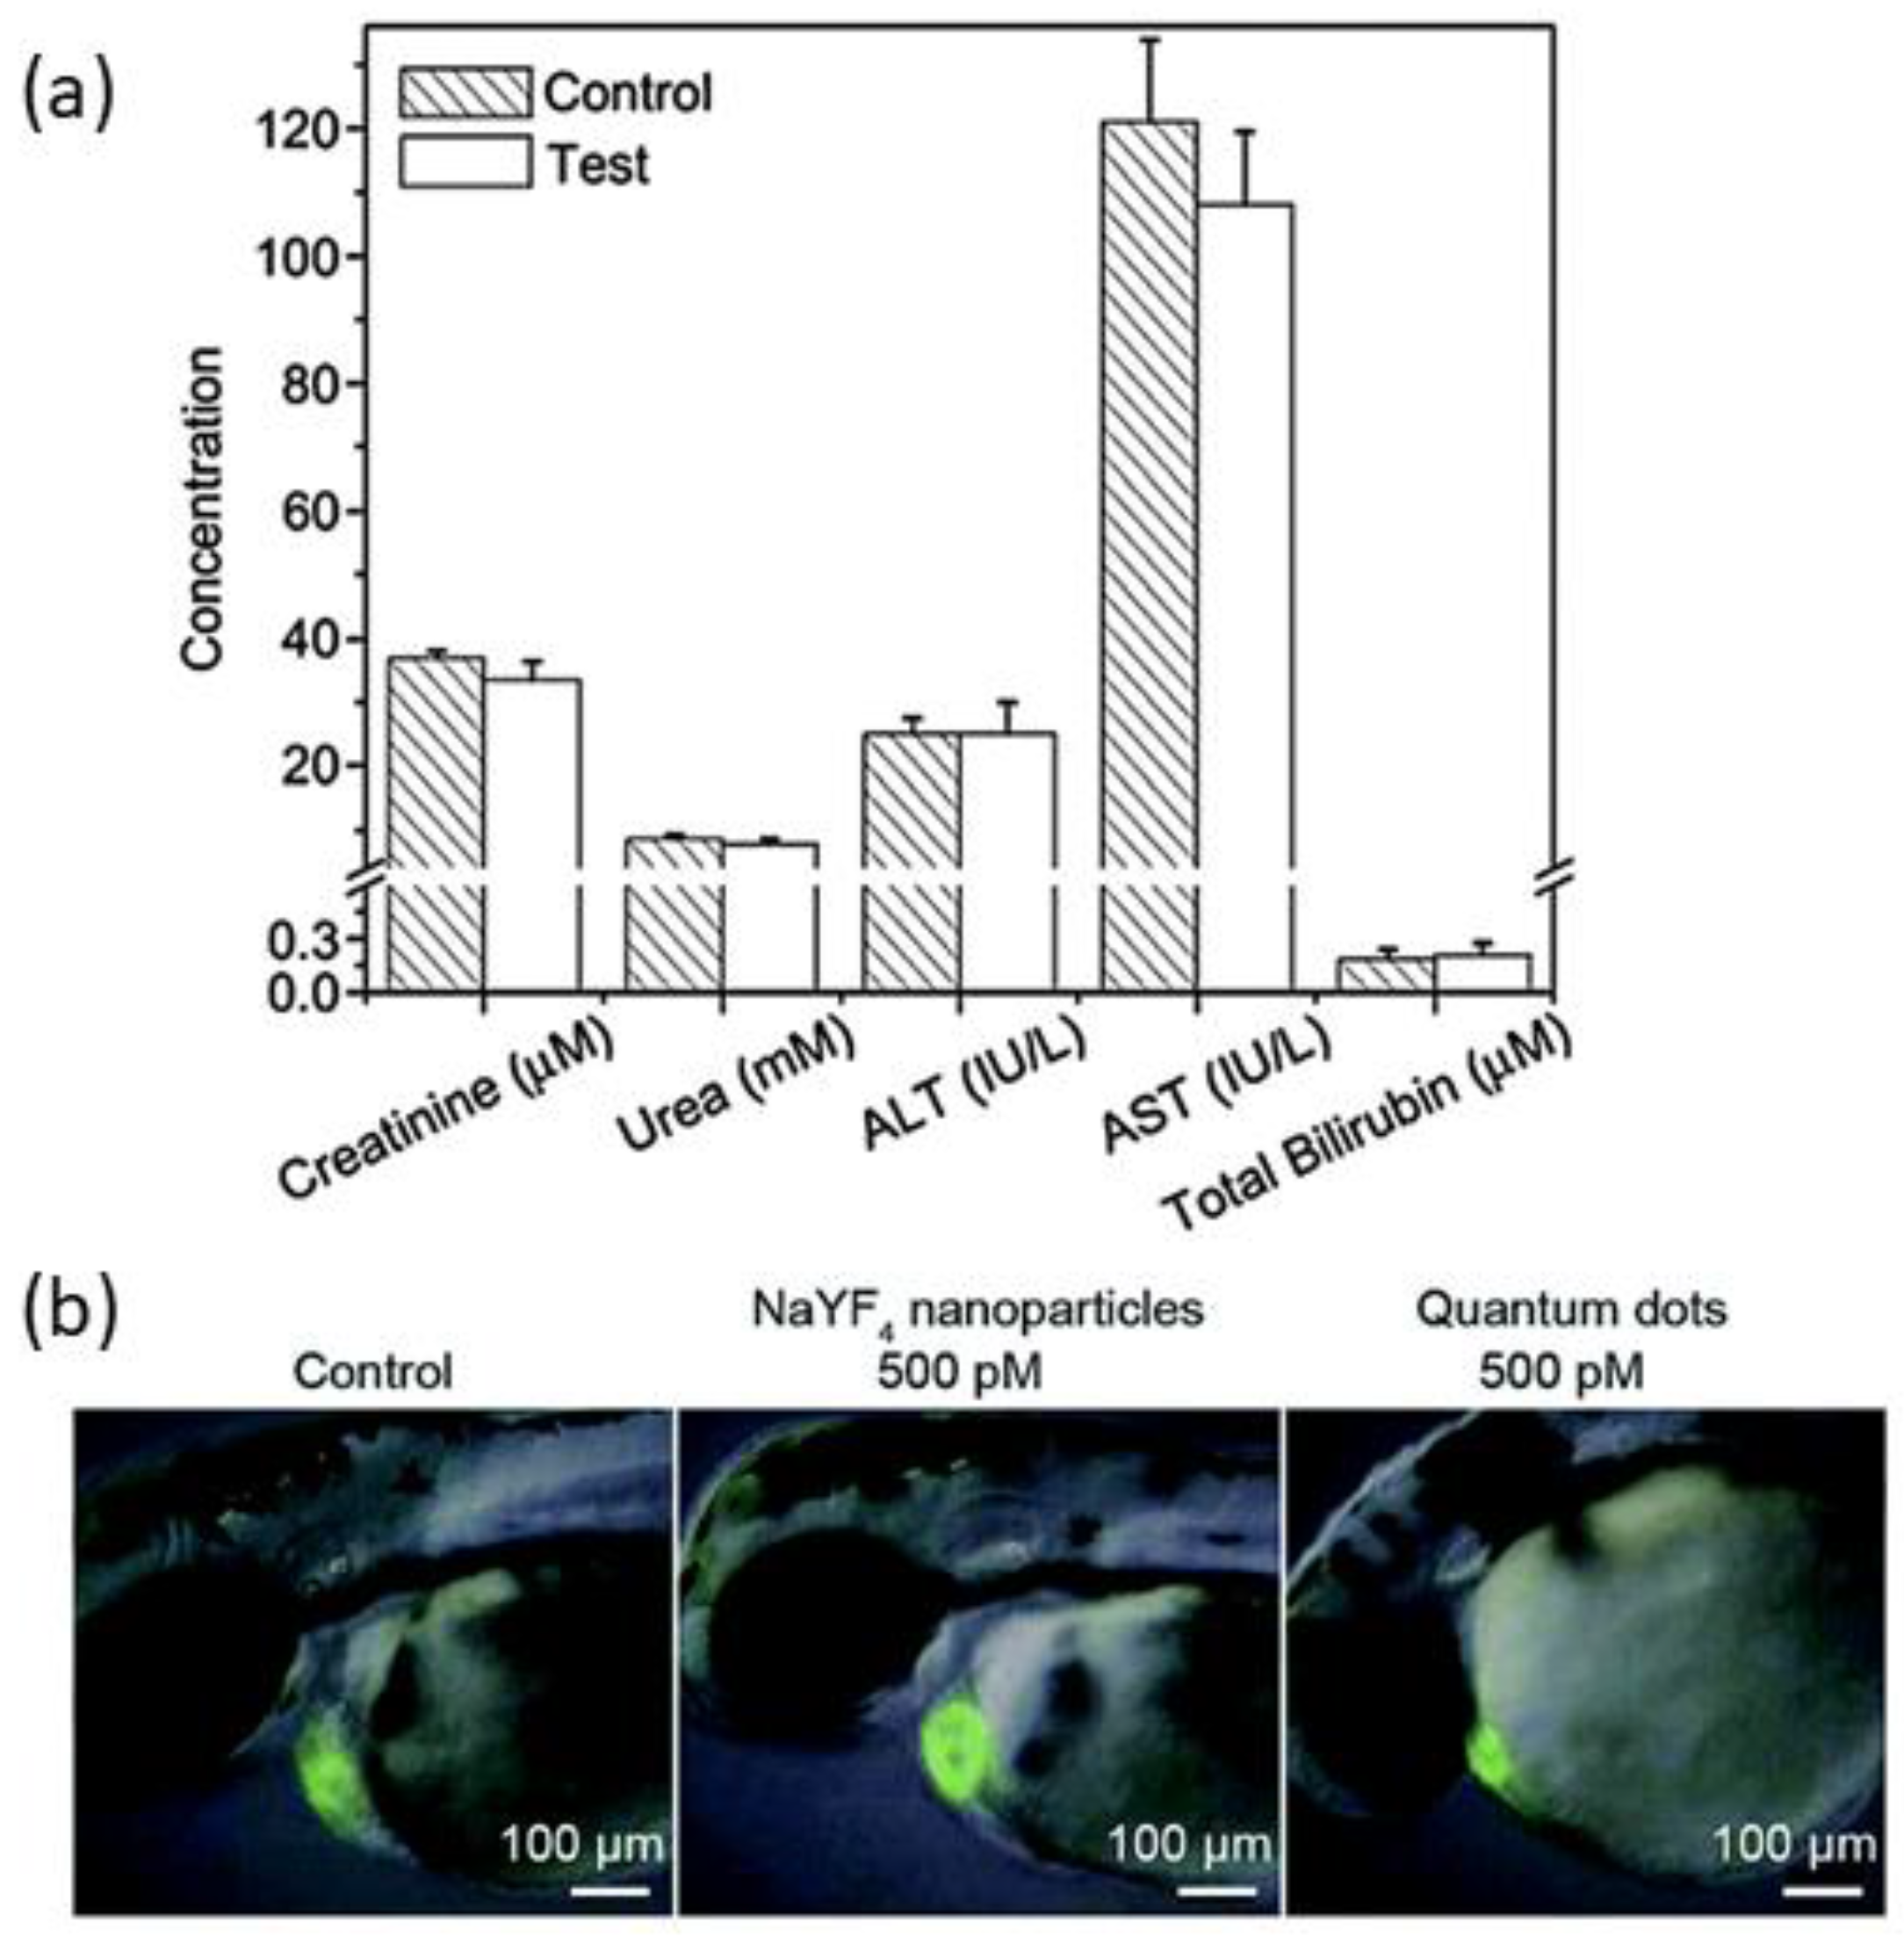

- Jang, G.H.; Hwang, M.P.; Kim, S.Y.; Jang, H.S.; Lee, K.H. A systematic in-vivo toxicity evaluation of nanophosphor particles via zebrafish models. Biomaterials 2014, 35, 440–449. [Google Scholar] [CrossRef] [PubMed]

- Hauck, T.S.; Anderson, R.E.; Fischer, H.C.; Newbigging, S.; Chan, W.C. In vivo quantum-dot toxicity assessment. Small 2010, 6, 138–144. [Google Scholar] [CrossRef] [PubMed]